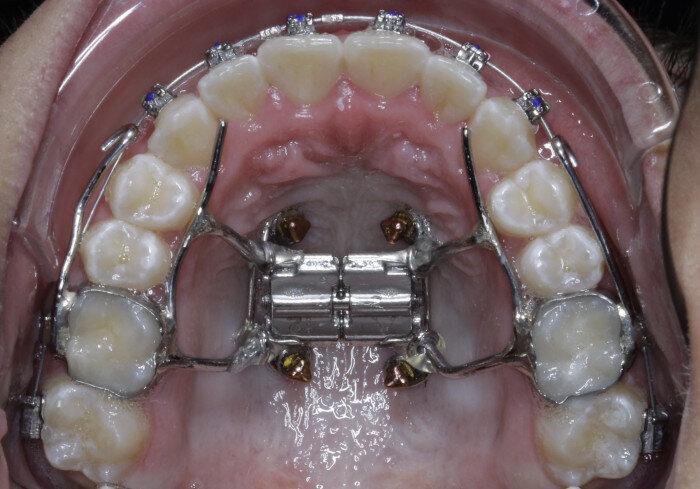

Case 5: Skeletal expansion

In cases where absolute maxillary expansion is desired with little to no dental side effects, maxillary anchorage with TADs is a wonderful solution. This allows for sutural expansion that has little to no dental compensation. Many designs exist for TAD placement with expansion. In some cases, a tissue-borne expander is used with no anchorage on the molars. This is typically used to encourage the maximum amount of skeletal expansion when dental tipping is undesired (Figs. 52 & 53). In cases where molar anchorage is desired, a banded approach can be used in conjunction with TADs (Figs. 54–59).

Fig. 52

Fig. 53